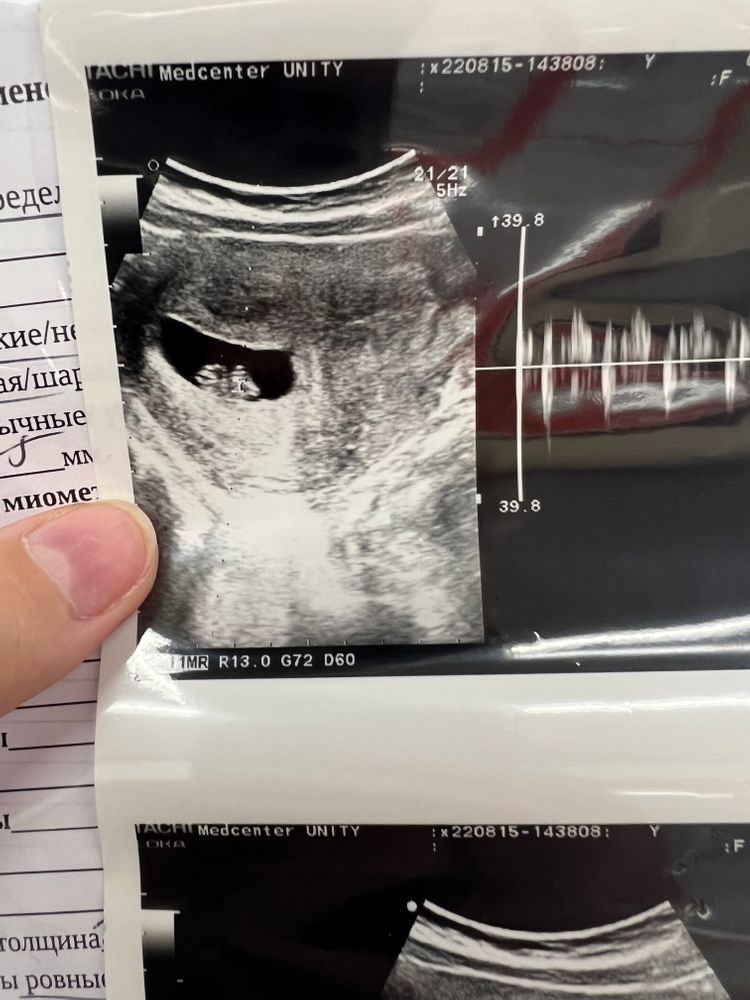

В итоге сходила на узи😁

Растёт малышочек 😍😍😍 Как приятно видеть ❤️

Тонус - это когда матка в напряжении, она сокращается, а не расслаблена как должна быть) Не критично, но нужно не перегружать себя и отдыхать побольше

Светлана Курканина, 8+3 😊☺️